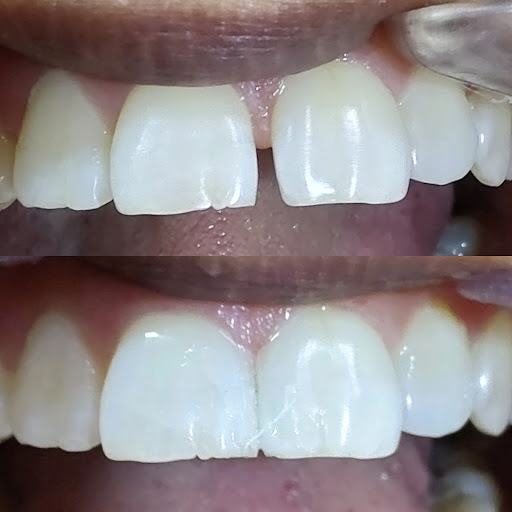

A visit away solution to your Any tooth and gums related problems. Root canal treatment, Asthetic and cosmetic treatments, Orthodontic treatments, teeth cleaning and whitening are done with best material and instruments. For permanent teeth Implants are available in affordable price it can be done for a single missing tooth or for all teeth in o...

Gallery